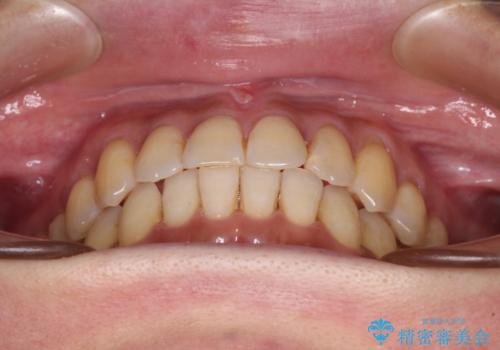

- 前歯のクロスバイトが気になり、インビザラインによる矯正治療を希望して来院された患者様です。

上顎側切歯(上の真ん中から2番目の歯)が舌側転位している場合、インビザラインでは仕上げきれないことが多く、更には無理して動かそうとすると歯髄壊死を起こすリスクが高いと言われています。

インビザラインで歯列を移動する前に、上顎前歯をワイヤー矯正で整え、その後上下歯列をインビザラインにて矯正治療を行うこととしました。

舌側転位している側切歯特有の、切縁の位置が不揃いであったり、根元が内側に引っ込んだ状態であったりという、インビザライン独特の仕上がりになることなく、きれいに整った歯列とすることができました。